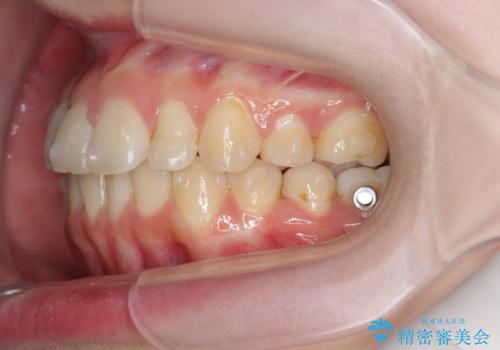

右側奥歯は上顎が相対的に前方に位置し(上顎前突)、そのため前歯の角度も突き出たようになり出っ歯のように見える状態でした。

マイクロインプラントを用いて、上顎奥歯を後方に移動させることで噛み合わせ・前歯の角度を改善していきます。

少し時間はかかりましたが、しっかりと綺麗な歯並びに仕上げることができ、大変喜んでいただくことができました。